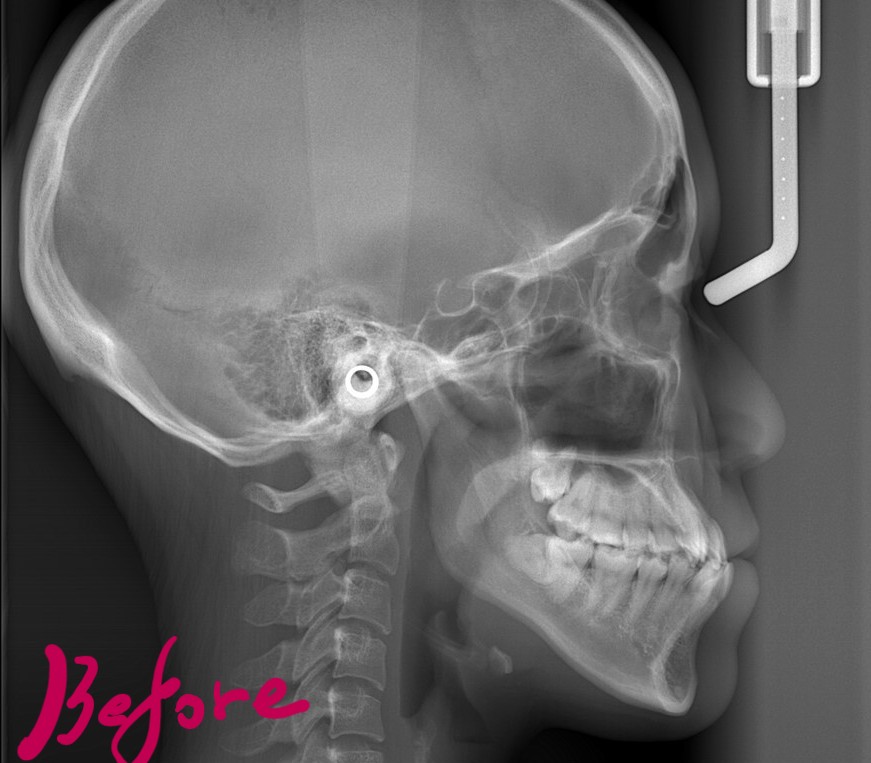

【Before】

レントゲン写真で確認すると、

#2.骨格的に下顎前突(受け口)傾向

レントゲン写真でも矯正治療前後を比較してみましょう